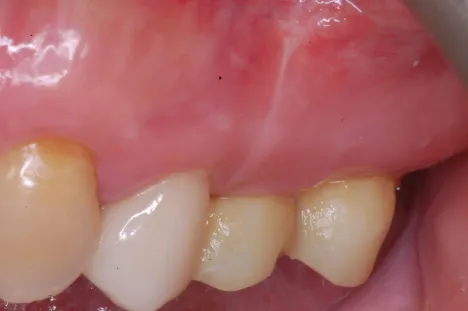

Dr.Megas_Fig.6

Fig. 6. Intraoral photograph 7 months after surgery.